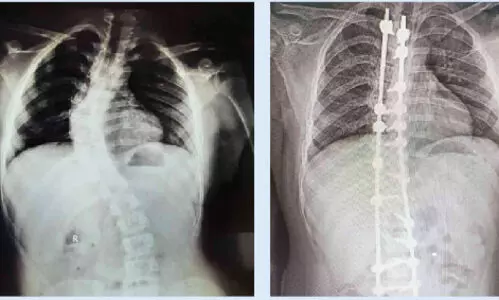

മുളങ്കുന്നത്തുകാവ്: ഗവ. മെഡിക്കൽ കോളജ് ആശുപത്രിയിൽ ആദ്യമായി നട്ടെല്ല് നിവർത്തുന്ന...